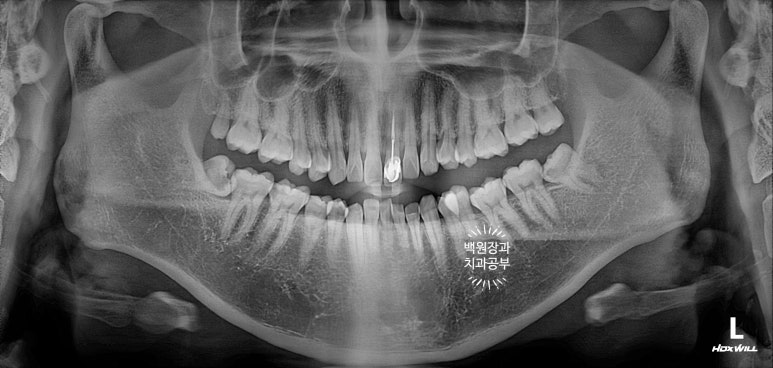

40대 남자 환자분이셨고, 처음 뵈었을 때 왼쪽 위 대문니가 이미 부러진 상태로 오셨었어요.

엑스레이를 보시면, 내원 당시 기둥까지 빠졌던 치아를 그 자리에 끼워놓으셨기 때문에 마치 치아가 멀쩡한 것 처럼 보입니다만, 이미 사용하기 어려운 지경의 상태였습니다.

이런 중절치 부러짐은 은근히 많이 볼 수 있는 증례입니다.